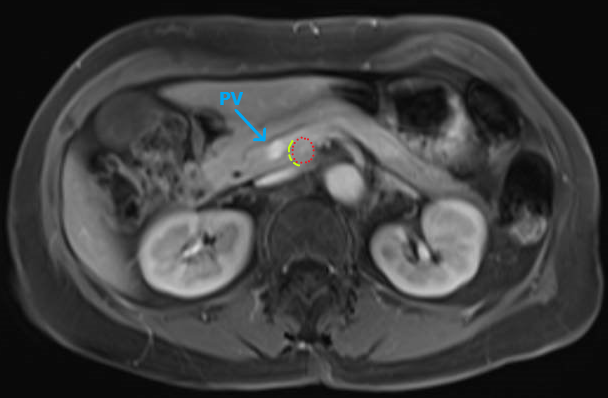

Laparoscopic resection of functioning PNET (red) at the uncinate process between the PV (blue) and SMA. Combined cephalad and caudal approach to uncinate to define transection line (yellow) #SoMe4Surgery